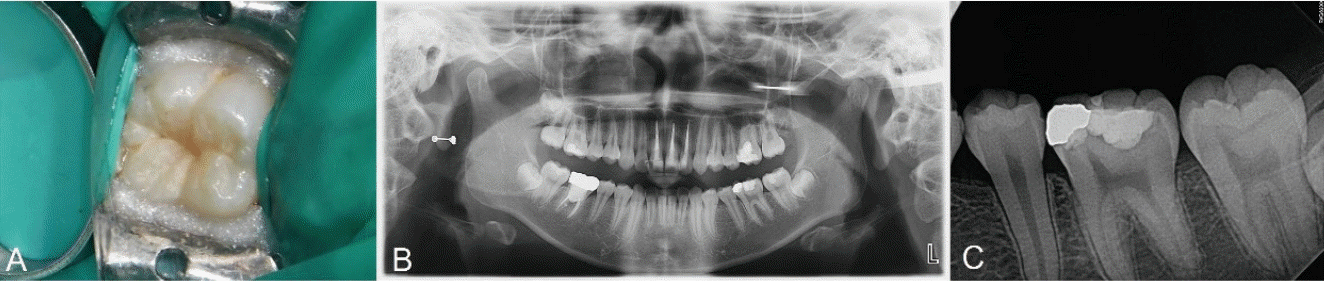

Fig. 3.

Initial examination radiograph and clinical photograph. A. No loss of tooth structure was observed. B. Preoperative panoramic radiograph. C. Caries of dentin is seen on olwer left second molar.